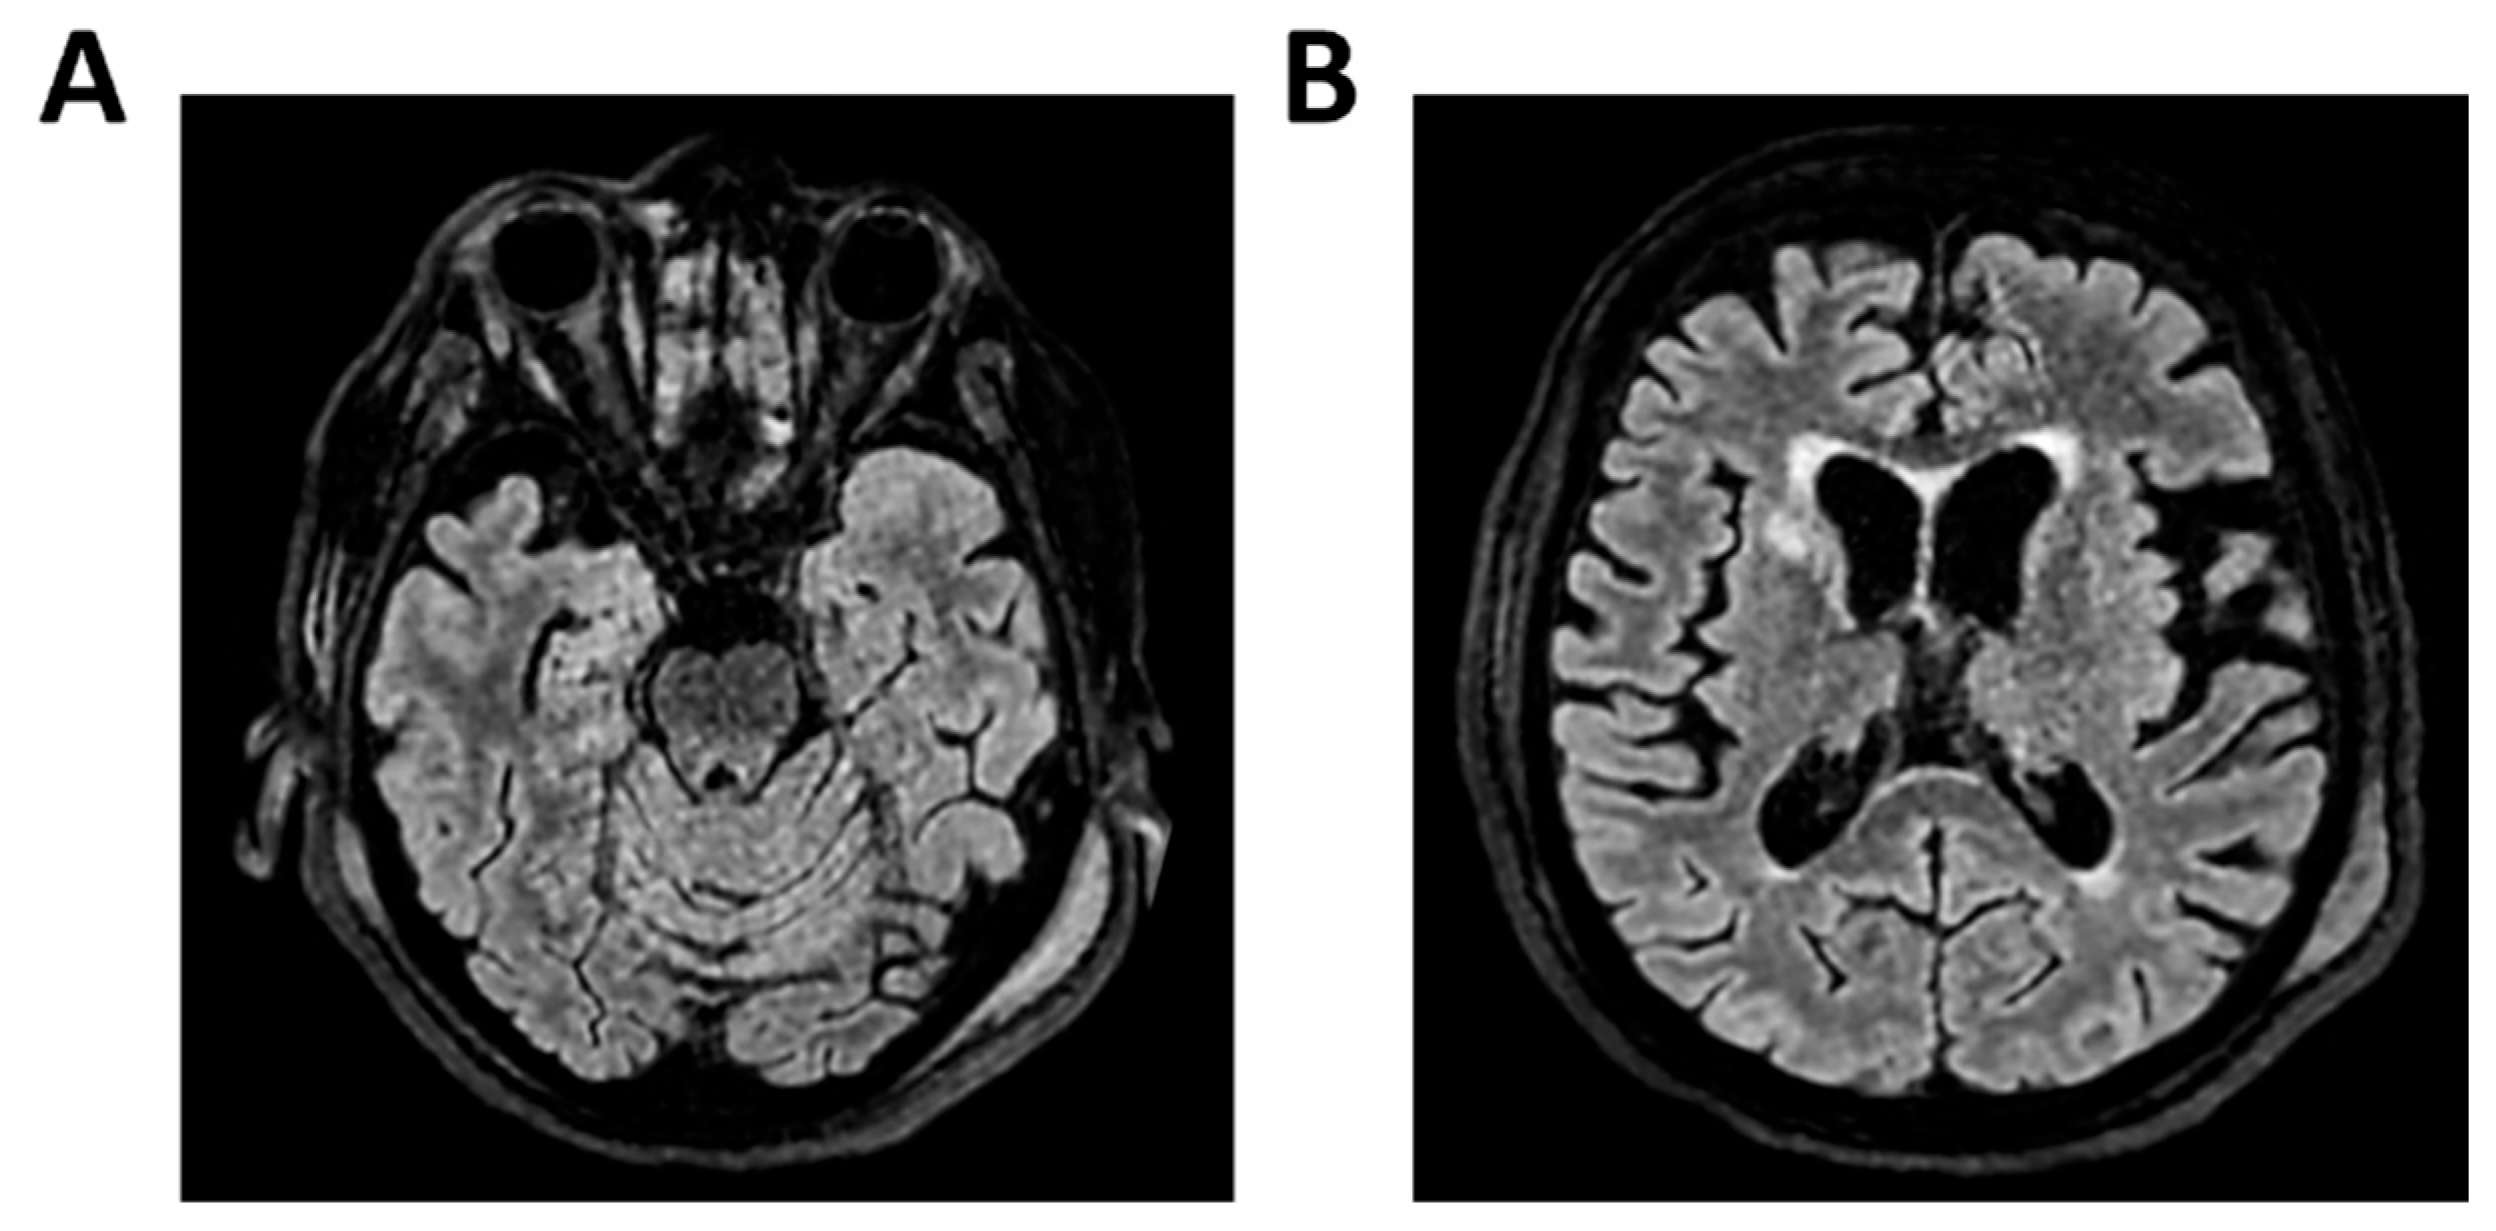

Figure 1.

MRI of patient 1 group 1. A 74-year-old woman with a history of atrial fibrillation, ischemic heart disease, anxiety-depressive syndrome, and hypertension was found at home in a stuporous state. She had experienced asthenia and fever in the preceding days and had initiated ciprofloxacin treatment. On arrival, laboratory exams showed leukocytosis (11,930/mm3, 90.4% neutrophils), elevated INR (1.92), and markedly increased inflammatory markers. Arterial blood gas revealed hypoxemia (pO2 55 mmHg), requiring mechanical ventilation with 35% FiO2. Brain CT was unremarkable, showing no acute lesions or signs of raised intracranial pressure. Chest CT revealed bilateral posterior-basal consolidations with air bronchograms (more severe on the left), a smaller consolidation in the left upper lobe, and bilateral pleural effusions, consistent with bronchopneumonia. A lumbar puncture was initially contraindicated due to coagulopathy. Due to worsening neurological status (GCS 6), the patient was transferred to the ICU, intubated, and underwent lumbar puncture. On day 2, TCCD showed PI values of 0.62 (right) and 0.71 (left), with no signs suggestive of intracranial hypertension. (A) 3D axial FLAIR sequence shows multiple bilateral hyperintense areas, without mass effect. (B) Some of these present diffusion restriction in axial DWI sequence with the largest located in the left middle and superior frontal gyrus. There is also a subtle pachymeningeal enhancement in the bilateral fronto-temporal region. Supratentorial and infratentorial ventricular system is normal in size and configuration, with no midline shift or hydrocephalus.